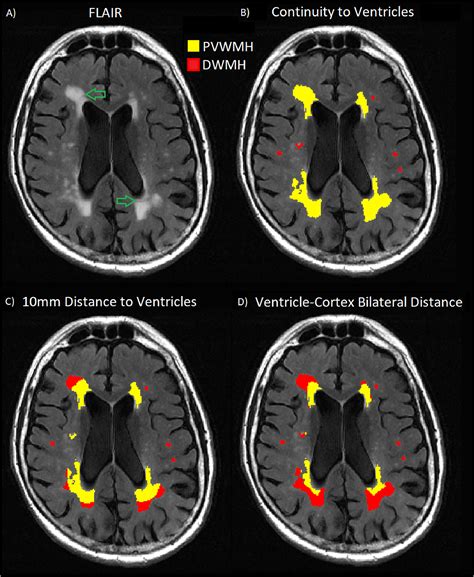

Periventricular White Matter Disease occurs when the integrity of this myelin or the underlying axons is compromised in the area surrounding the brain's ventricles—the fluid-filled cavities within the brain. This is often categorized under the broader umbrella of small vessel disease. When blood flow to these deep, sensitive areas of the brain is reduced, often due to stiffening or narrowing of the small arteries, the tissue begins to show signs of damage. Radiologists often describe these areas as "hyperintensities" or "lesions" on an MRI scan.

When you look at a medical report, you may see the severity of these white matter changes graded. A common system used by neurologists is the Fazekas scale. Understanding where your results sit on this scale can help you have a more informed discussion with your healthcare provider.